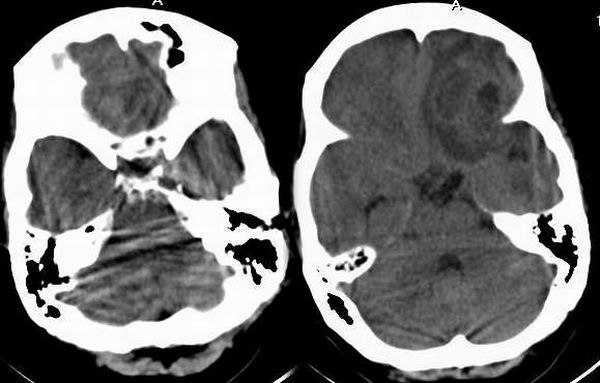

女,59岁,反复头痛月余,加剧二天.

左侧额叶见多房混杂不规则病灶,占位明显,周围见轻度水肿带,左侧侧脑室受压变窄及大脑镰向右移,增强后见病灶壁环行厚薄不均强化,其内低密度未件强化,首先考虑多房脑脓肿,此区脑脓肿多来源于鼻窦炎查鼻窦。2。胶质瘤2-3级,不太支持胶质瘤征象近皮质侧壁太厚,边缘规正。未见典型花环状。

以下是引用cmg在2005-4-9 21:26:00的发言:[br]该病灶发生于左侧前颅窝底部,有占位表现,增强扫描可见多个环状强化影,不知该患者有没有发热症状及副鼻窦炎的表现?考虑该例为鼻源性脑脓肿可能性大。